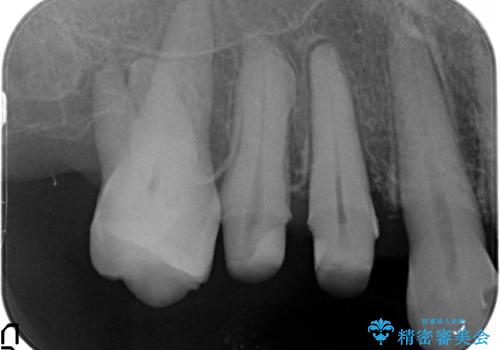

- 歯のぐらつき、歯周病の検査を希望され来院されました。

検査の結果、強い歯ぎしりによる歯の周囲の骨の吸収が認められたため歯槽骨の再生・歯周ポケットの除去・力に対抗する連結補綴・補綴前処置としての小矯正を計画します。